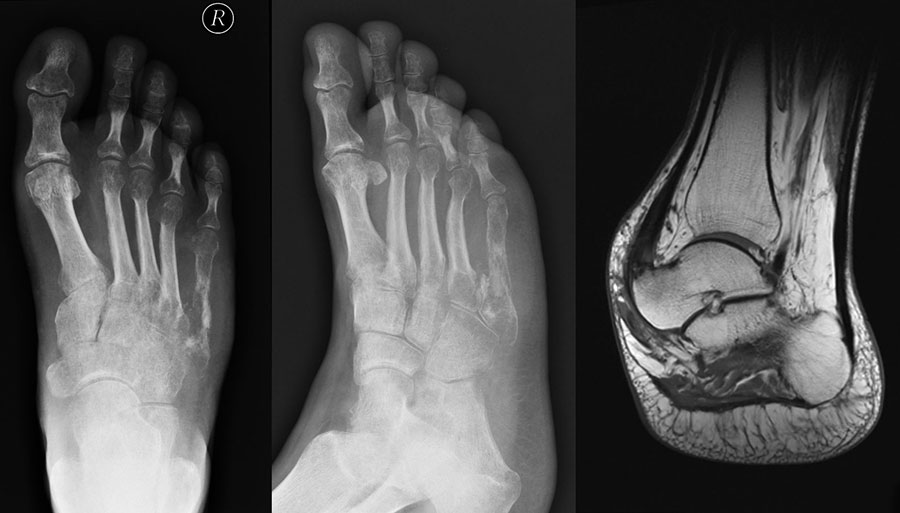

Enchondrom

Das Enchondrom ist der häufigste Knochentumor im Bereich von Hand und Fuß und nach dem Osteochondrom der zweithäufigste gutartige Knochentumor überhaupt. Die geschlechtliche Verteilung ist ausgeglichen, Enchondrome finden sich meist bei Patienten zwischen 20-40 Jahren. Dieser chondrogene Tumor verhält sich meist asymptomatisch, kann aber durch eine Knochenexpansion und Schwellung sowie Spontanfrakturen (Abb. 17) auffallen. Radiologisch zeigen sich in der Regel gut abgrenzbare Osteolysen, Matrixverkalkungen sind typisch aber nicht obligat. Die MRT zeigt typischerweise eine annähernd flüssigkeitsäquivalente Signal­qualität mit niedrigen Signalintensitäten in T1 und hoher Signalgebung in T2, die Binnen­struktur weist eine für chondrogene Tumoren typische Lobulierung mit KM-Aufnahme auf.

Im Gegensatz zu Osteochondromen ist die Lage von Enchondromen nicht auf die Metaphyse beschränkt. Sie finden sich auch im Bereich der Epi- und Diaphysen. Die kurzen tubulären Knochen der Metatarsalia und Phalangen sind bevorzugt betroffen. Hier findet sich die Läsion typischerweise im Bereich der proximalen Phalangen oder distalen Metatarsalia, eine Ausbreitung auf die gesamte Diaphyse ist von hier aus jedoch nicht ungewöhnlich. Die Möglichkeit einer malignen Entartung (Chondrosarkom) ist im Bereich der Metatarsalia und Phalangen im Vergleich zu den langen Röhrenknochen und platten Knochen extrem selten 33. Die übliche Therapie besteht in einer gründlichen Curettage. Je nach Größe des Defekts und Schwächung der Kortikalis kann die Transplantation eines stabilisierenden kortiko­spongiösen Spans notwendig werden. Zusätzliche osteosynthetische Verfahren sind nur selten erforderlich.